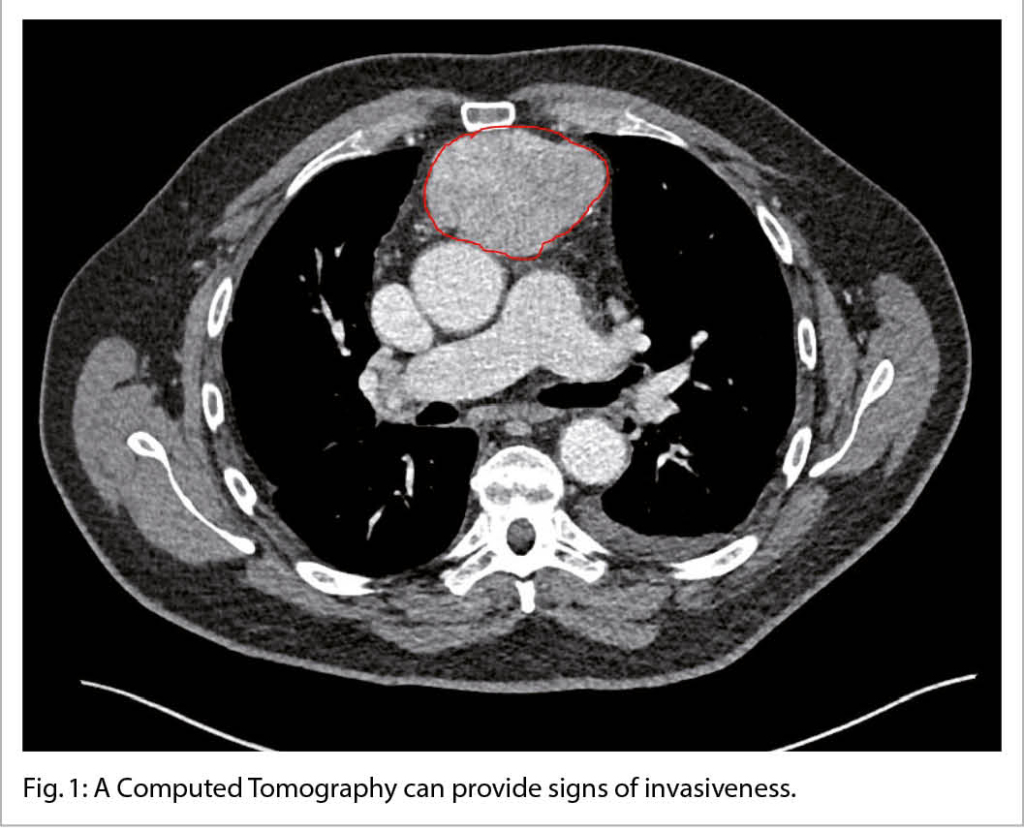

Roughly 30% of thymoma patients have no symptoms and the diagnosis is made incidentally based on radiological findings (2). Most of thymomas are visible on chest radiography as an ovoid mediastinal mass abutting unilaterally (very rare even bilaterally) and, on the lateral view, as a mass located in the retrosternal compartment. A Computed Tomography (CT) is considered the gold standard not only because is highly evocative of the diagnosis (fig. 1) but can also provide, especially when performed with intravenous contrast, signs of invasiveness (irregularity, unclear margins, an incomplete capsule, pleural or pericardial effusion, invasion of surrounding structures).